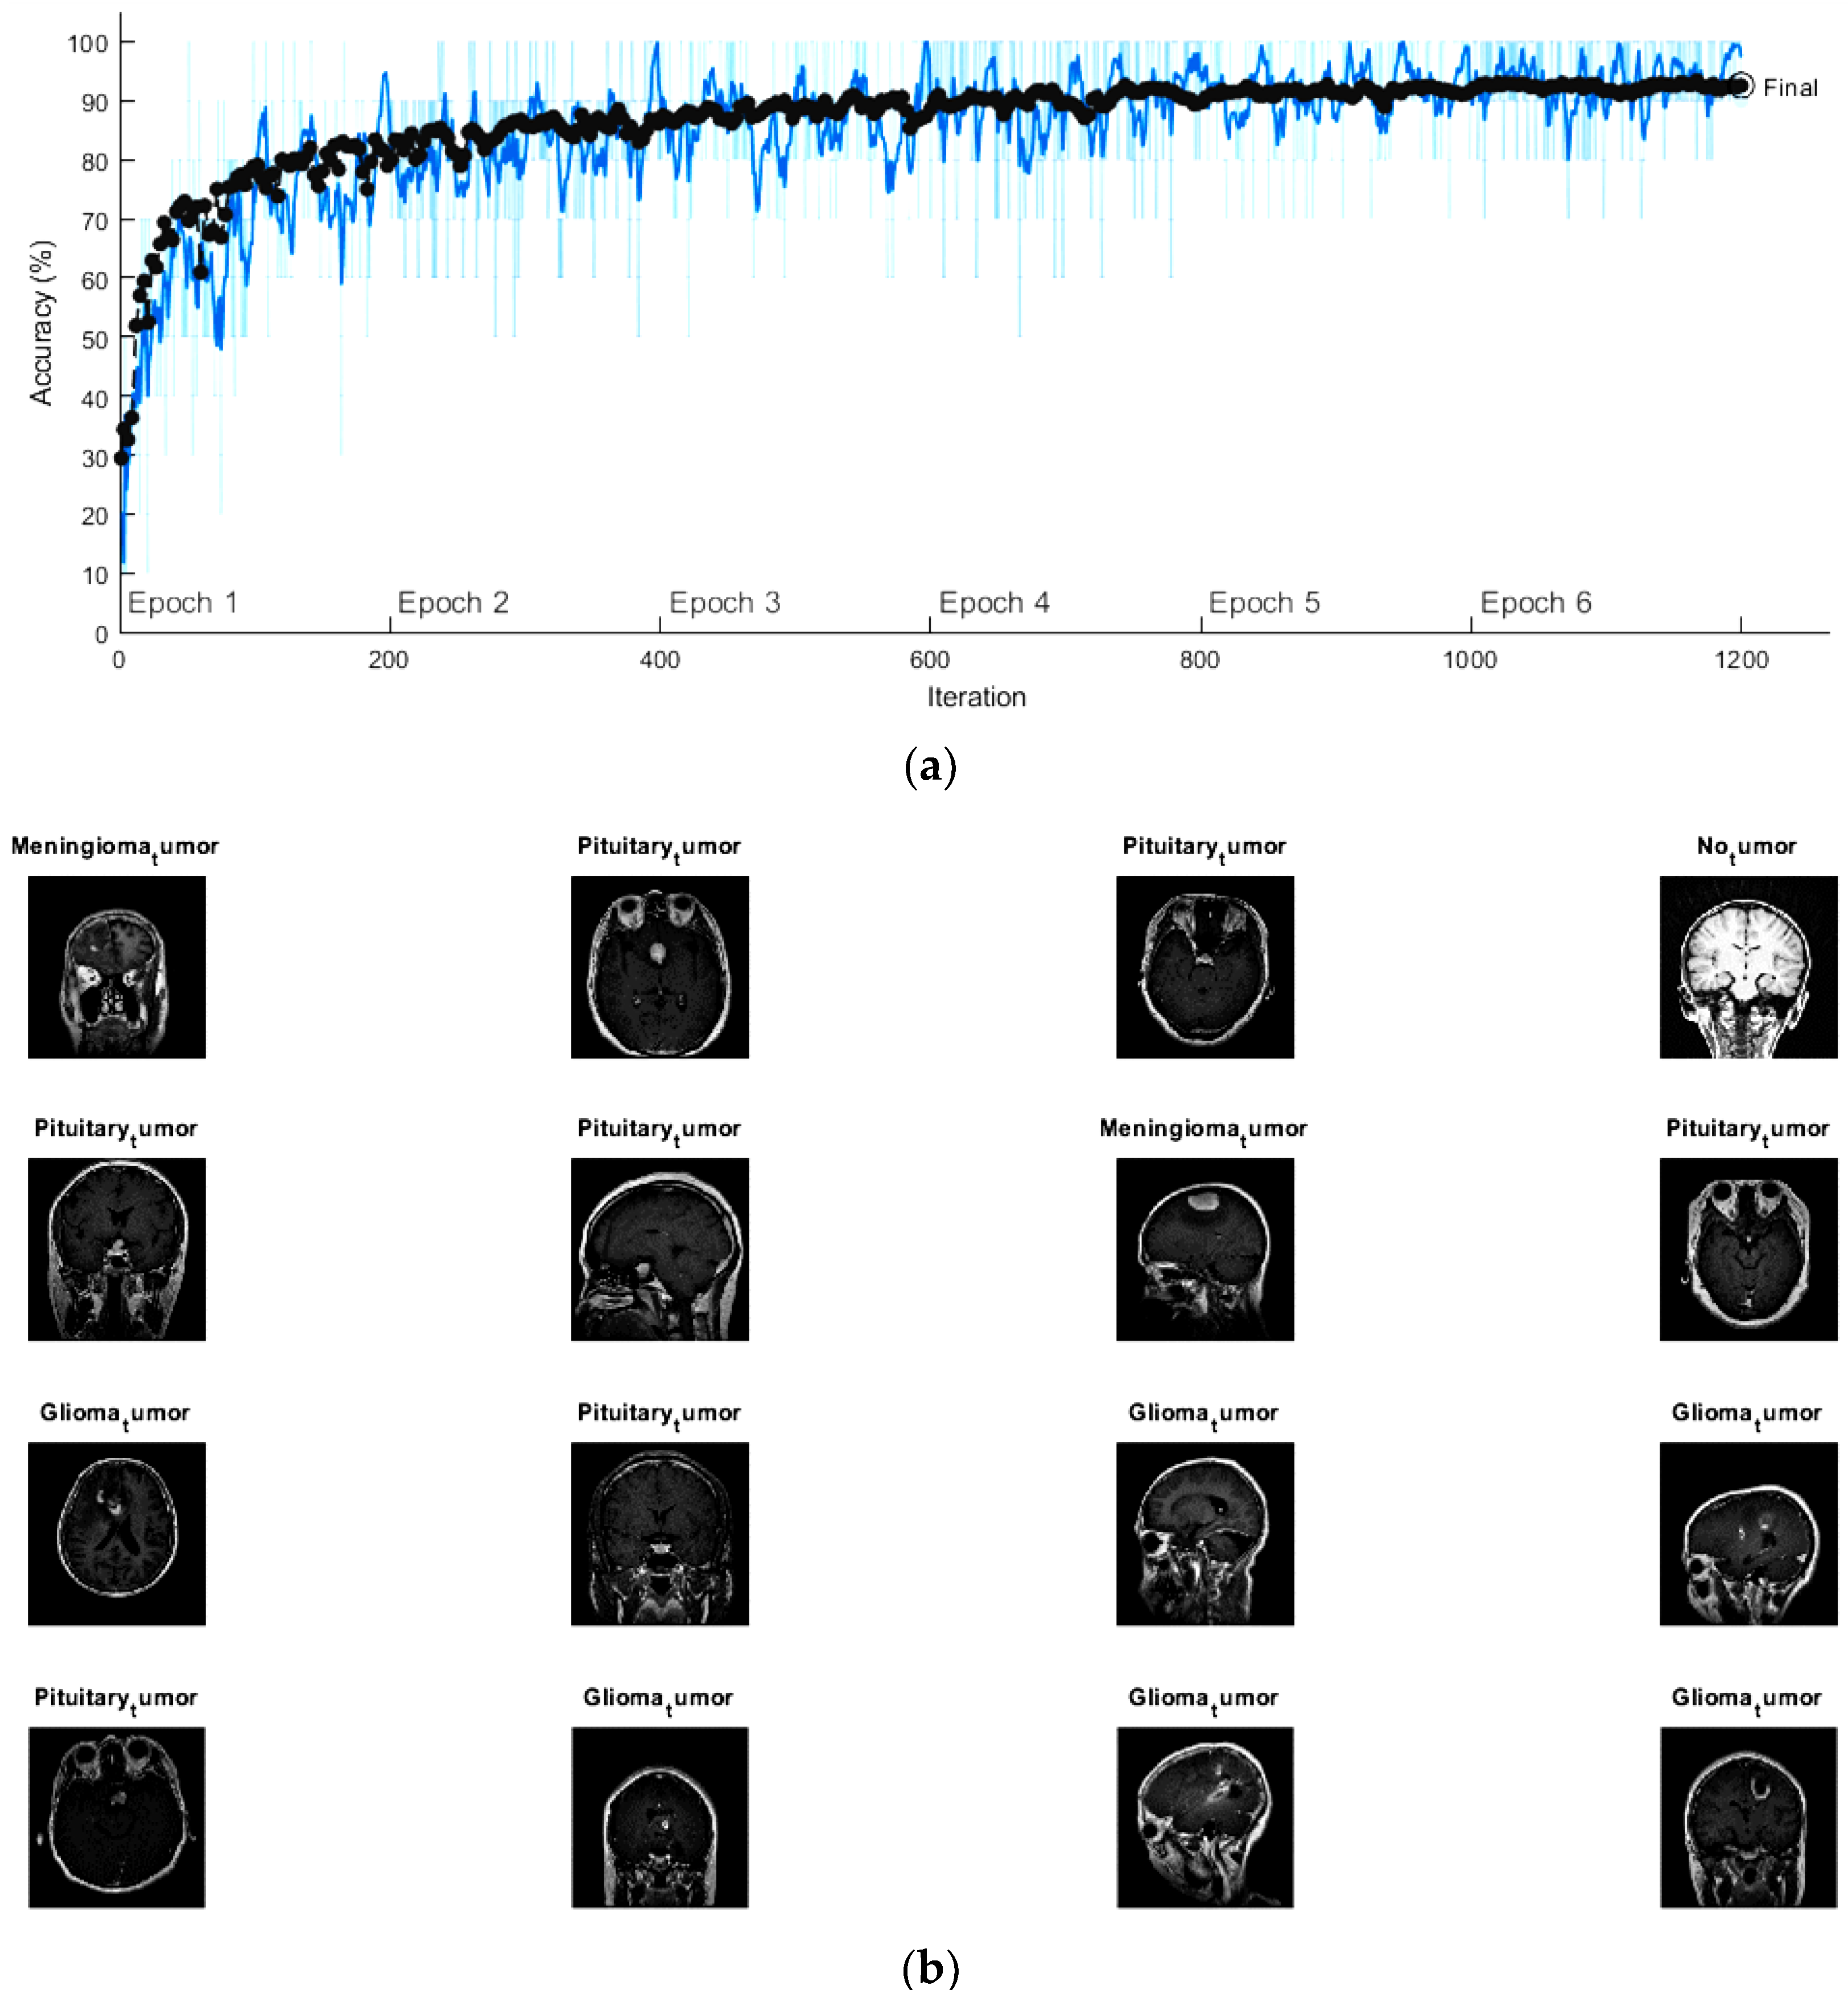

The initial learning rate, the maximum epochs and the minimum batch size of the fine-tuned GoogleNet were set to be 10-4, 6, and 10, respectively. In addition, the activation function used for this network was the stochastic gradient descent momentum (SGDM) function. Figure 7a shows the progress graph of this network using the training and validation sets. It became clear that the accuracy of the validation was reaching 91.5% after 1200 iterations with execution time totaling 4 h, 45 min, and 2 s. Several MRI scans from the validation set with the predicted labels are displayed in Figure 7b.

Figure 7.

(a) The progress graph of the pre-trained GoogleNet for the brain tumors and (b) some validated brain tumors with their predicted labels using fine-tuning GoogleNet.